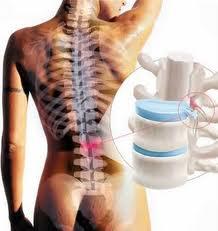

Hérnia de Disco

A coluna é formada por um conjunto de 33 vértebras desde a região do pescoço até a bacia. Serve para sustentar o tronco e membros.Cada vértebra é separada por um DISCO INTERVETEBRAL que age como um amortecedor (colchão de proteção) diminuindo o impacto das forças que atuam na coluna. Permite o movimento entre elas, impedindo […]